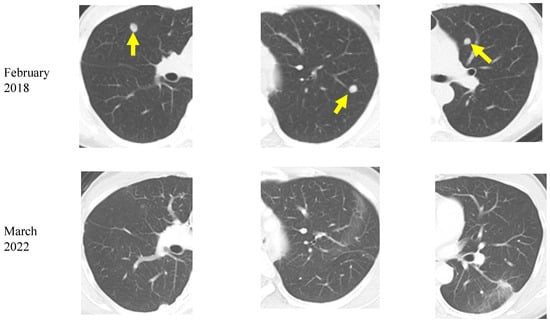

| 2 | F | 52 | Lung cancer | Adenocarcinoma | T2aN0M1b | Ongoing | 422 | 109 | alive |